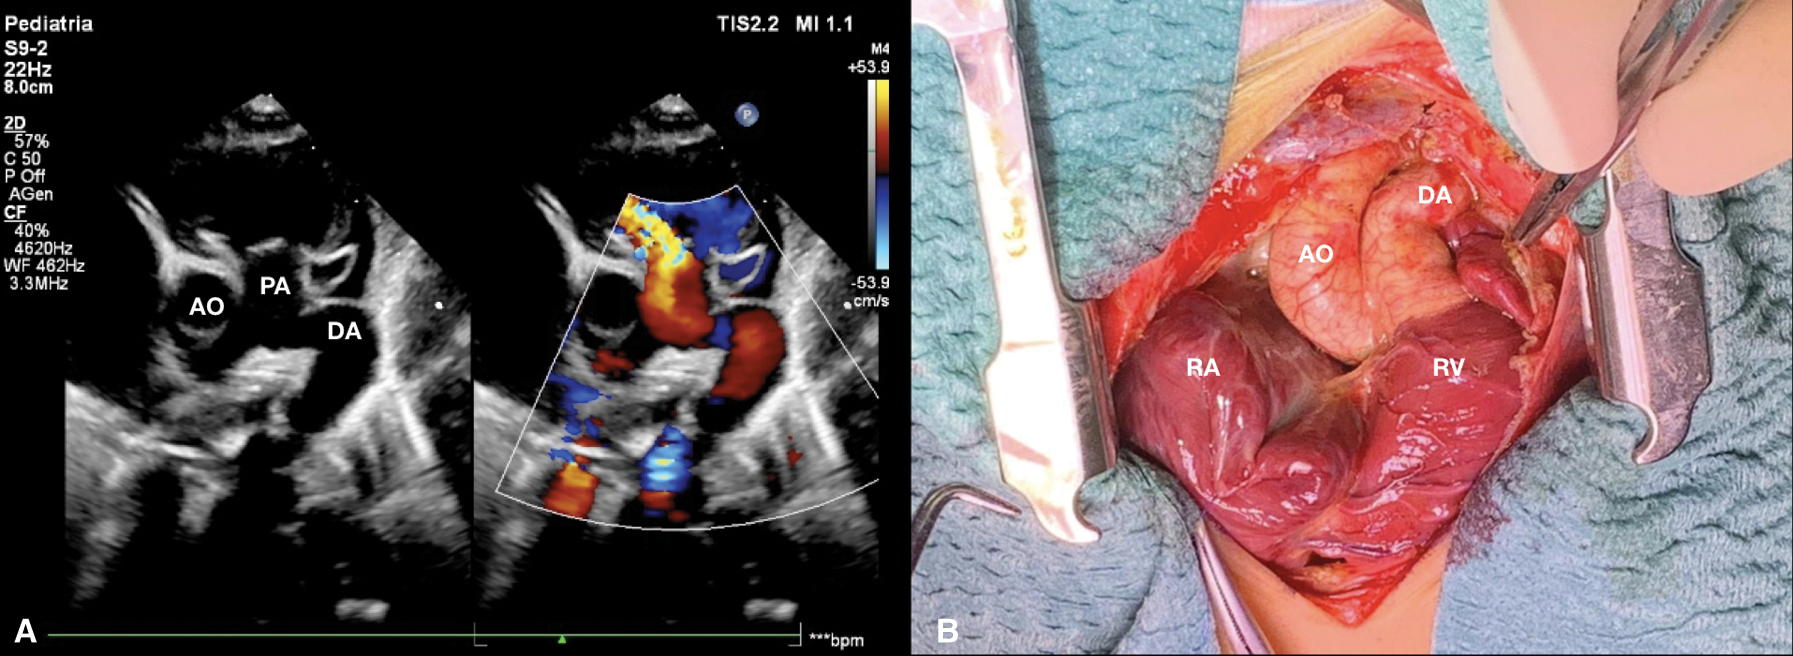

High intravenous dosage of Prostaglandin E1 (PGE1) was administered immediately. Chest X-ray showed severe cardiomegaly and wall to wall heart (Fig. 3A). After diuretic and dopamine therapy, TR improved from severe to trivial, but persisted functional PA with a thickened non-opening pulmonary valve without anterograde flow. Multidisciplinary team decision was to progressively reduce Prostaglandin’s dose and clinical observation. Clinical conditions progressively worsened with an imposing right heart failure characterized by ascites, hepatomegaly and anuria (creatinine: 2 mg/dl). Despite diuretic therapy and paracentesis drainage, we faced with further deterioration of clinical conditions such as increase lactates levels (6.5 mmol/l) and lower peripheral oxygen saturation of 75%. Serial echocardiograms documented persistence of a large PDA and limited opening of the pulmonic valve cusps, with initial mild anterograde flow. After 5 days of ineffective Ibuprofen administration, surgical PDA ligation was indicated and performed (Fig. 4). By sternotomy approach the first surgical findings were the evidence of cardiomegaly (Fig. 5) and a very large PDA that was ligated. Immediately after the procedure, progressive reduction of the right chambers’ enlargement and oxygen saturation improvement (up to 95%) was noted. Intraoperatory transesophageal echocardiography showed normal opening of the pulmonary valve and persistence of trivial tricuspid valve regurgitation.

Figure 4: (A) Short axis parasternal view after few days from birth shows patent ductus arteriosus with reversal flow and pulmonary regurgitation. (B) Surgical picture of ductus arteriosus before ligation. AO aorta, DA ductus arteriosus, PA pulmonary artery, RA right atrium, RV right ventricle

Figure 5: Surgical picture of wall to wall heart after ligation of ductus arteriosus. DA ductus arteriosus, RA right atrium, RV right ventricle